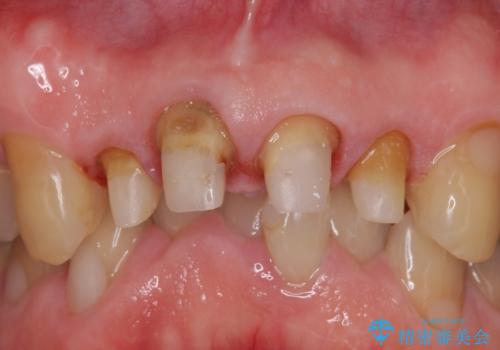

- 前歯の見た目が気になるといらっしゃった方の症例です。

再根管治療後、オールセラミッククラウンによる補綴を行いました。

右上2は歯茎のラインを整えるため歯周外科を行っております。